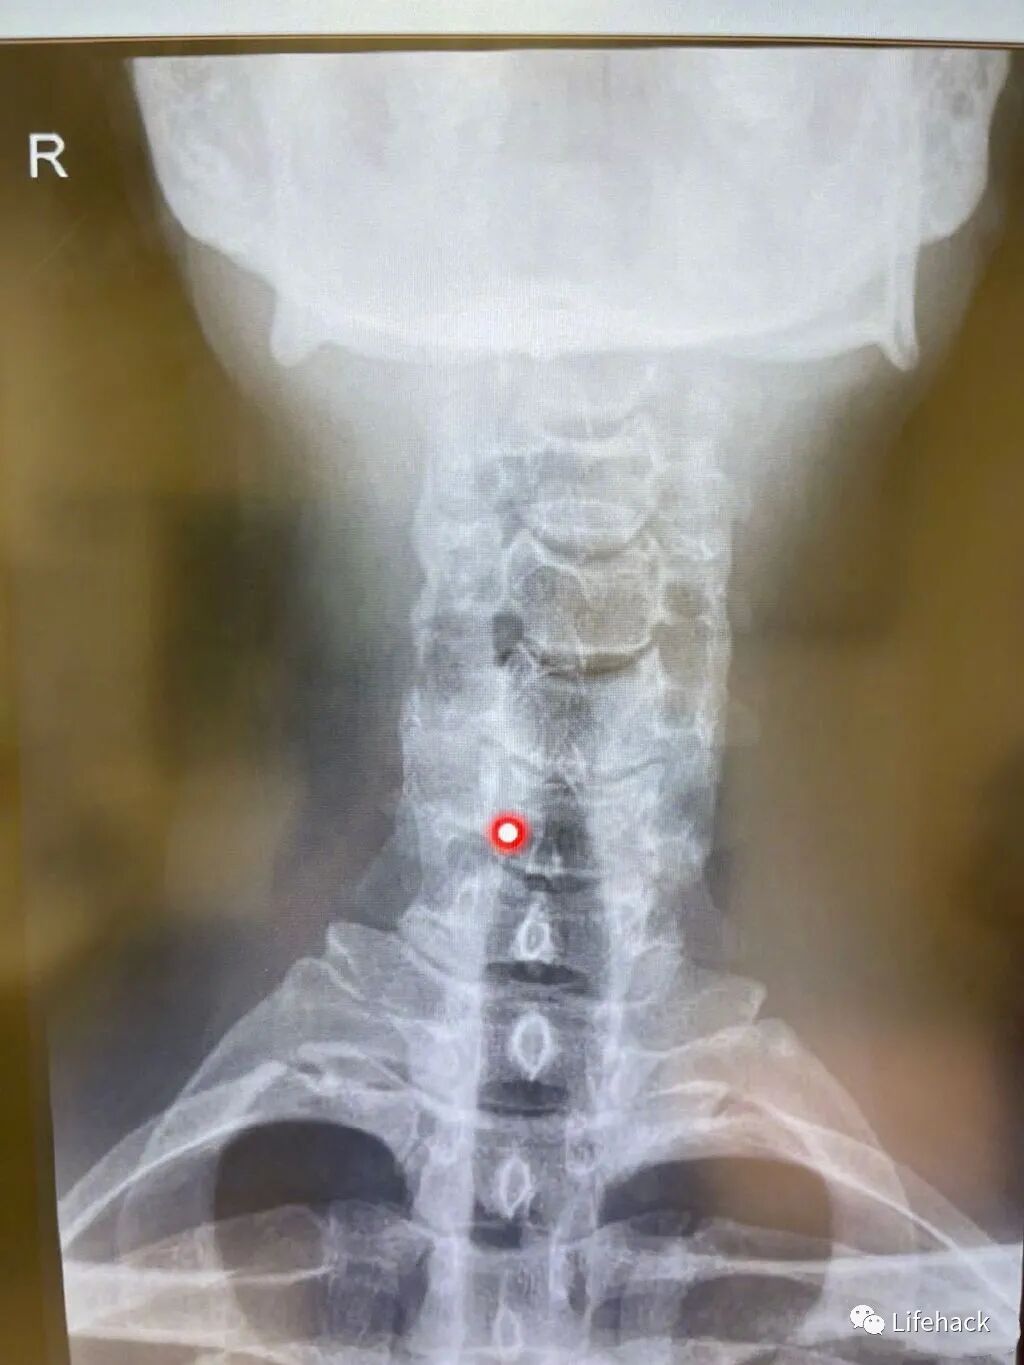

看到粉丝们对他的颈椎如此好奇,李治廷在下午还专门对此发了一条微博,调侃说要给大家演奏一首《我的颈椎》,并配上了两张他的颈椎CT片子。

片子中红点的位置应该就是他颈椎出问题的地方,简单直观地不难看出,这个位置就是长期保持低头姿势时,颈椎受压最大的位置所在!